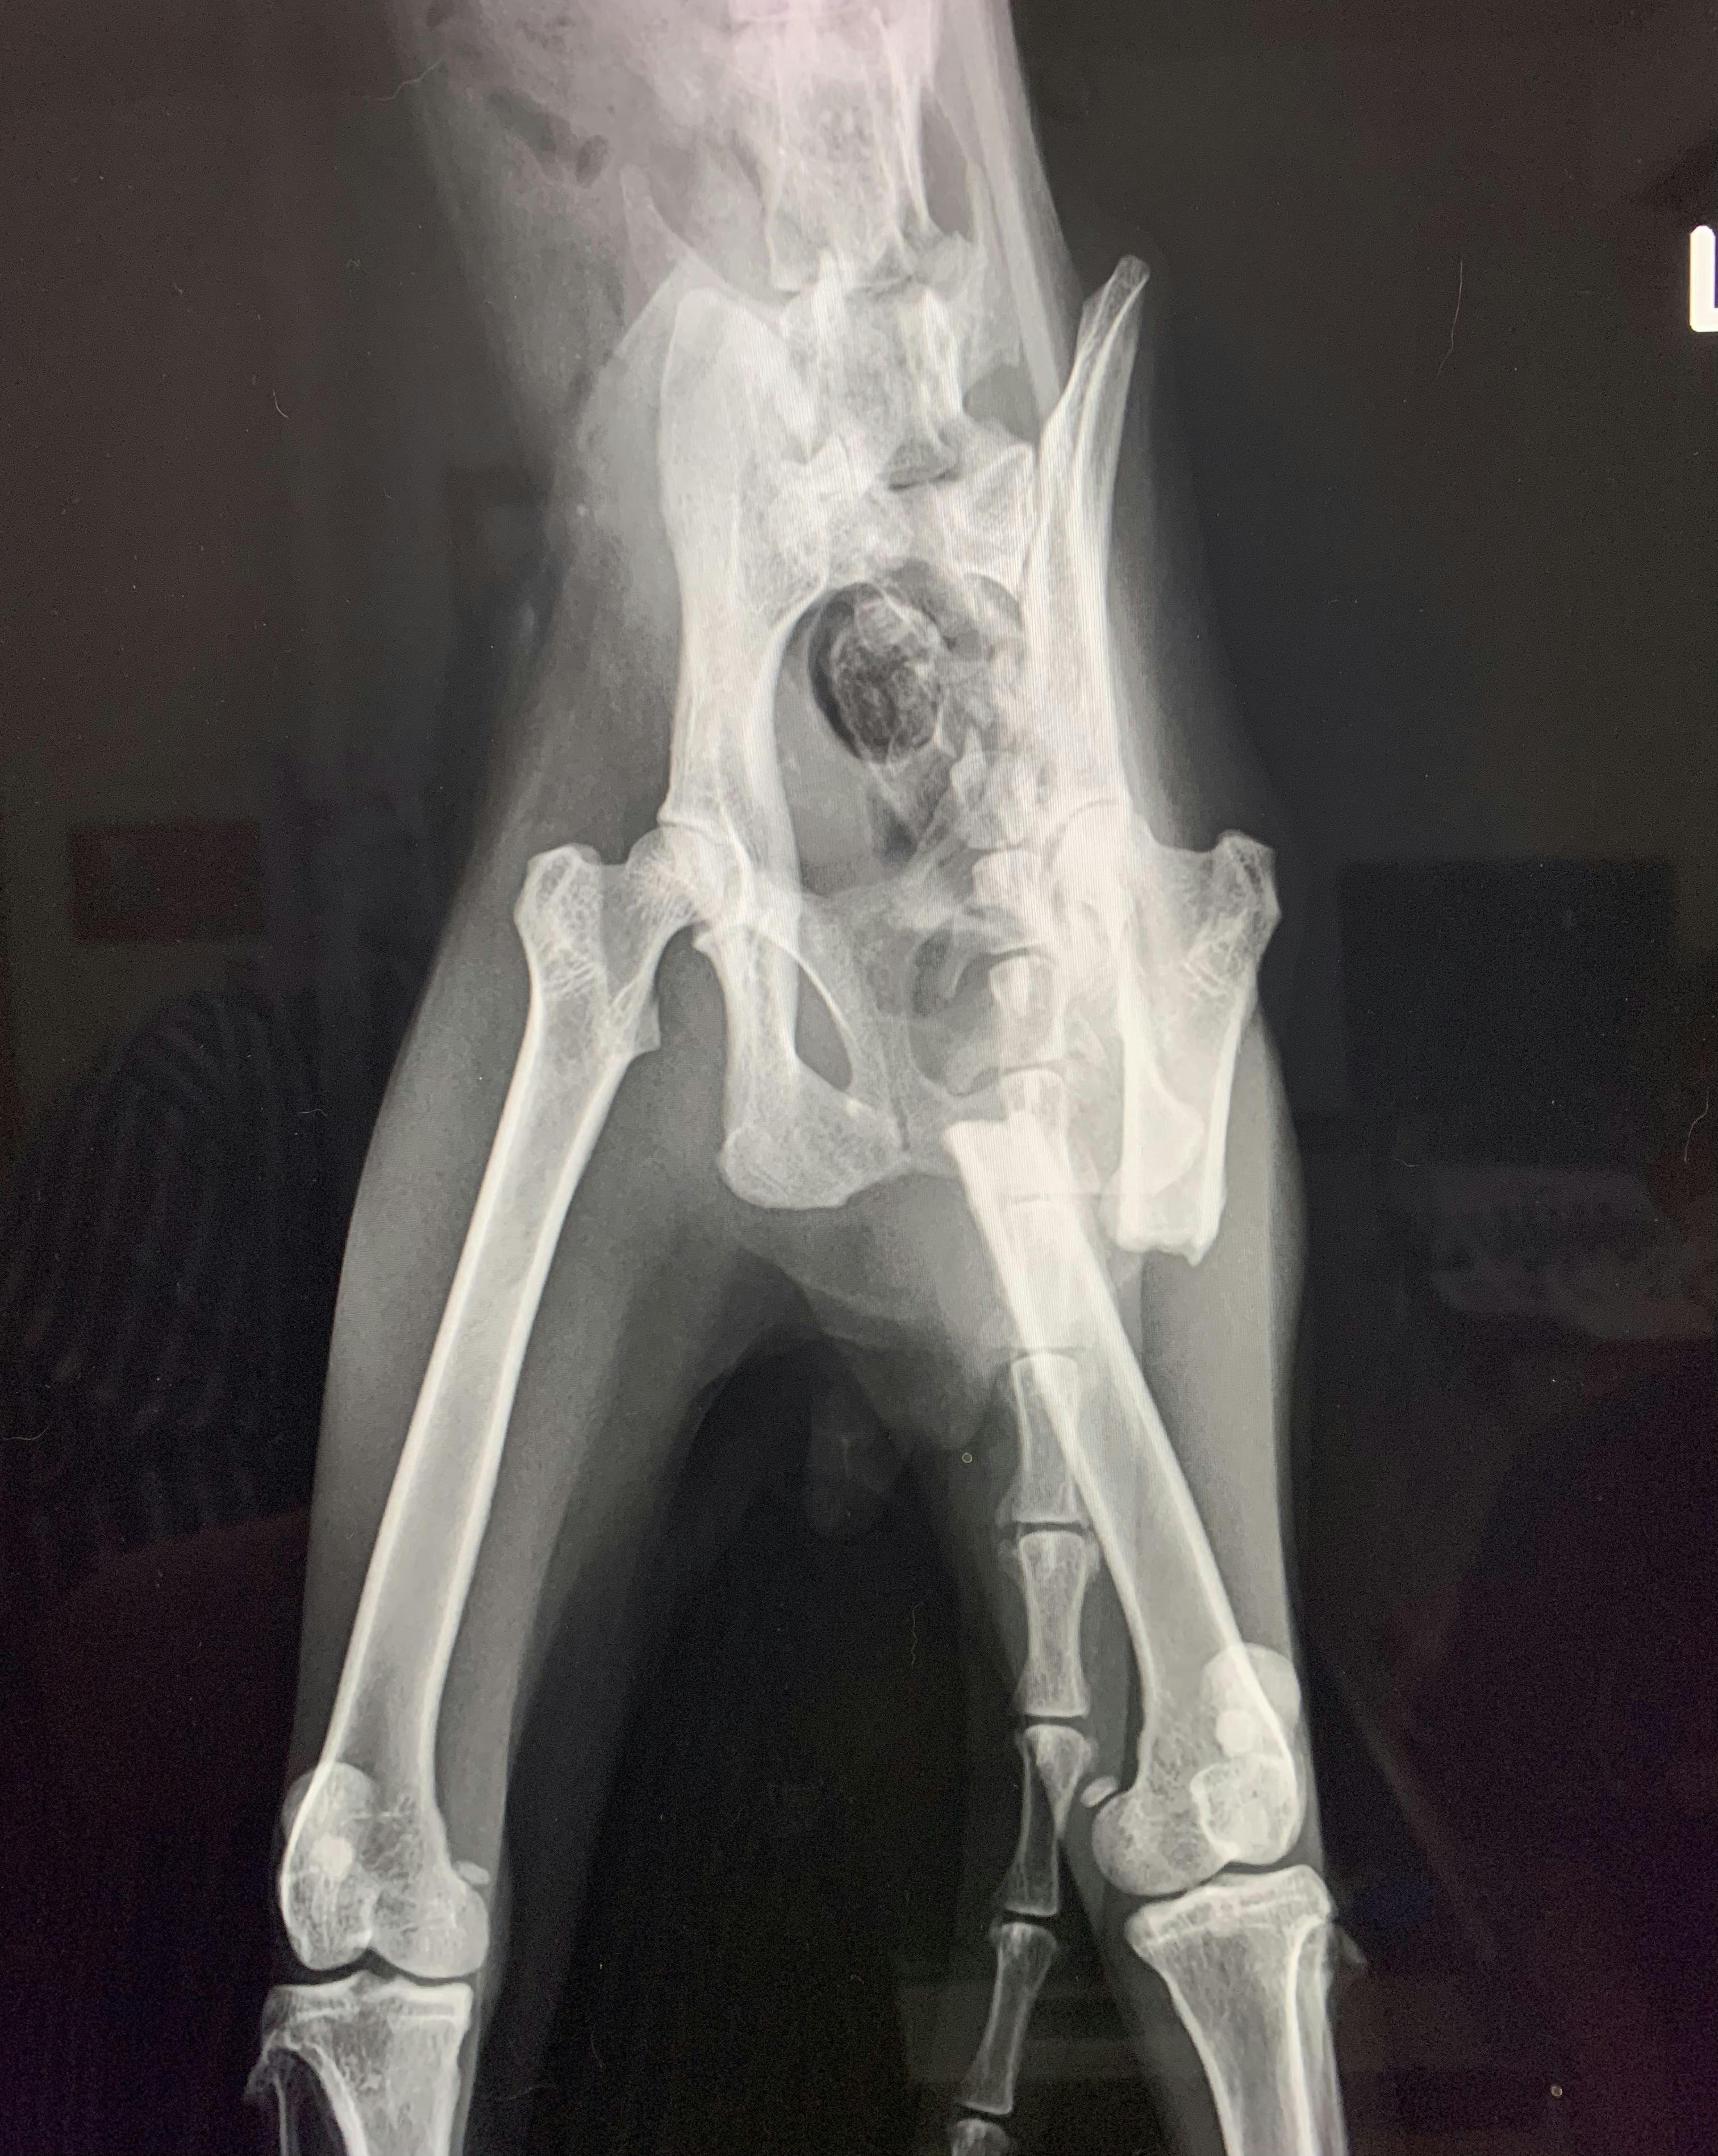

翌朝、動物病院での診断は、左大腿部の骨折!しかも骨折から数ヶ月が経過しており、それを補うための筋肉が発達したせいで、骨折した部分が筋肉により引っ張られ、左右に離れていました。このまま放置を続ければ左足の膝が逆向きになり重度の障害が残る大変な状況であることがわかりました。また、推定3歳の雄猫ですが、体重はわずか2キロしかありませんでした。

最短の日程で、手術は実施する運びとなりましたが、『まめおくん』は極度の貧血状態で、直ぐには手術することができませんでした。幸い1匹の猫ちゃんから輸血を受けることができ、8月30日の夜、手術開始となりました。大腿骨の一部切断、離れた骨をインプラントにより固定するという大手術でした。

手術は無事成功し、定期的なレントゲンによる経過観察を行っていくことになりました。

2021/12/30 13:42プロジェクト内容にも掲載させていただいておりました、骨折した状態で、2キロしか体重がなかった黒猫の『まめお』のその後の様子をお知らせいたします。8月30日に手術をしてから、数回に渡りレントゲン検査を行いました。その後、ウィルス性の風邪を患い、一時は食事が摂れなくなりましたが、クリスマス前には回復をいたしました。今では、我が家の4匹のお嬢様猫たちと見守りエリアから体調不良で保護したシニアの黒猫さんと6匹仲良く過ごしております。今回のクラウドファンディングは、活動の継続のためのフード費用と医療費のご支援でしたが、参考までに『まめお』の医療費の内訳と12月25日に体調不良のために保護をした『ひじき』の医療費内訳をご報告させていただきます。【まめおくんの医療費】保護後のメディカルチェック 17,160円手術 輸血 入院 159,570円検査後のレントゲン(8回) 26,400円ウィルス性の風邪治療・注射(3回) 7,260円・内服薬(16日分) 24,160円【ひじきくんについて】保護後のメディカルチェックは、猫エイズや白血病の検査と検便レボリューシャンプラスを含みます。今回、食事を4日間摂らないほど弱っていたための保護でしたので、詳細の血液検査と点滴と抗生剤の投与を行いました。私のTNRとその後の保護活動をご存知の病院なので、前回のまめおくんの手術費用同様、お安くして頂けております。ひじきくんの保護直後の医療費は、15,000円でした。体調次第では、これから通院が続く可能性もあります。活動当初は、TNRに必死で、一度、リリースした『さくらねこ』たちを家猫にできるとは思っていませんでした。ひじきくんが暮らしていた公園は、活動を始めた頃は5匹の子猫を含む11匹が暮らしていました。今では、2匹のさくらねこの親子が暮らしています。みなそれぞれに家族の一員として、あたたかい家庭で暮らしています。ひじきくんはもちろん、公園の2匹を含む見守りエリアの猫たちのみんなが、幸せな家猫になれるよう全力で頑張ります! もっと見るリターン到着後ご連絡について